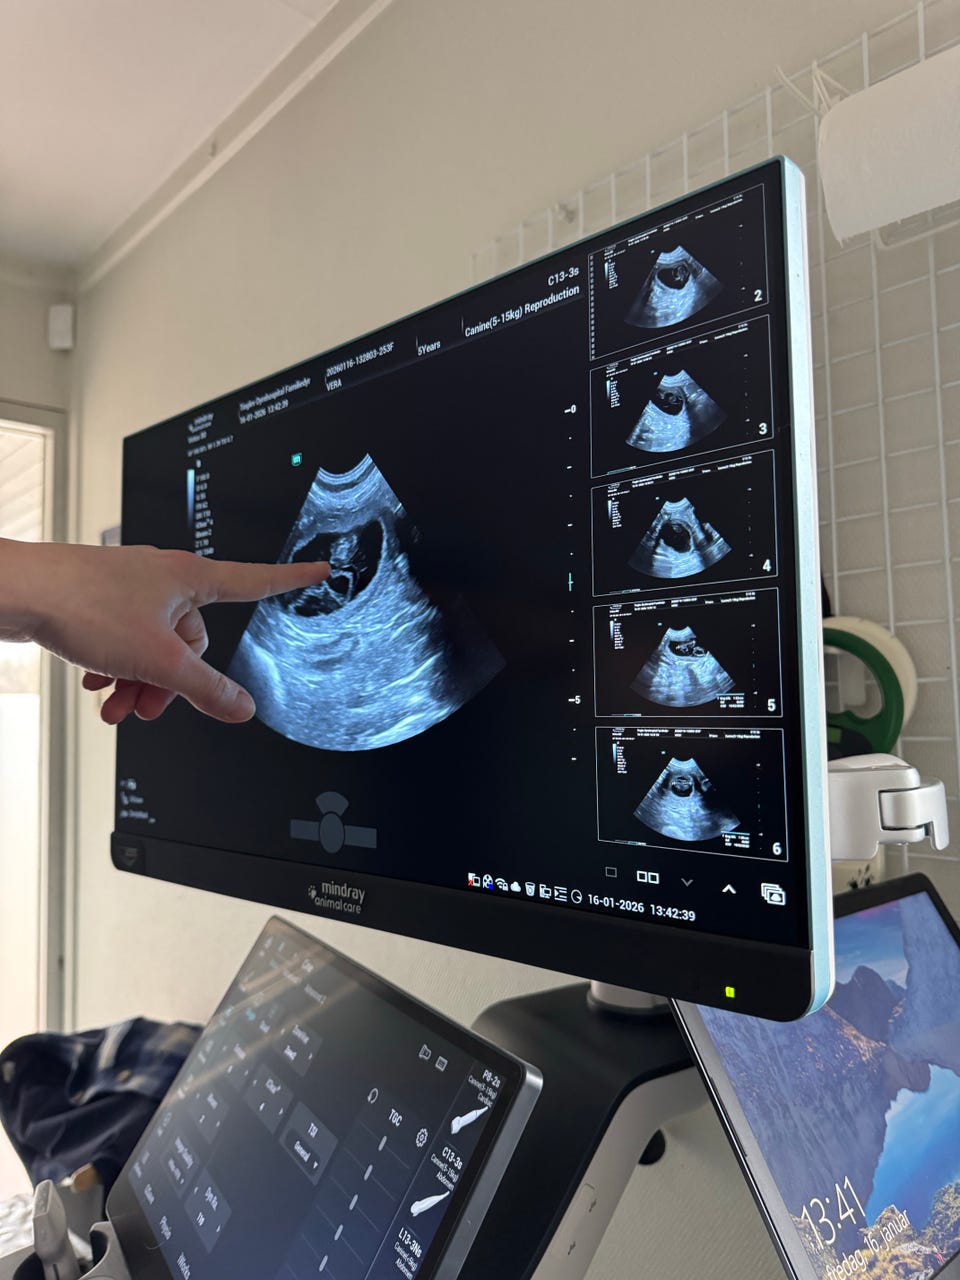

Vores dejlige Vera (7 kg) – en blanding af 1/2 puddel og 1/2 Cavalier King Charles – venter sit første kuld hvalpe med skønne Herkules(5,5 kg), som er ren puddel.

Forventet fødsel er den 18. eller 19. februar 💛

Mandag den 2. februar skal Vera røntgenfotograferes, så vi får at vide, hvor mange hvalpe vi kan forvente 🐶